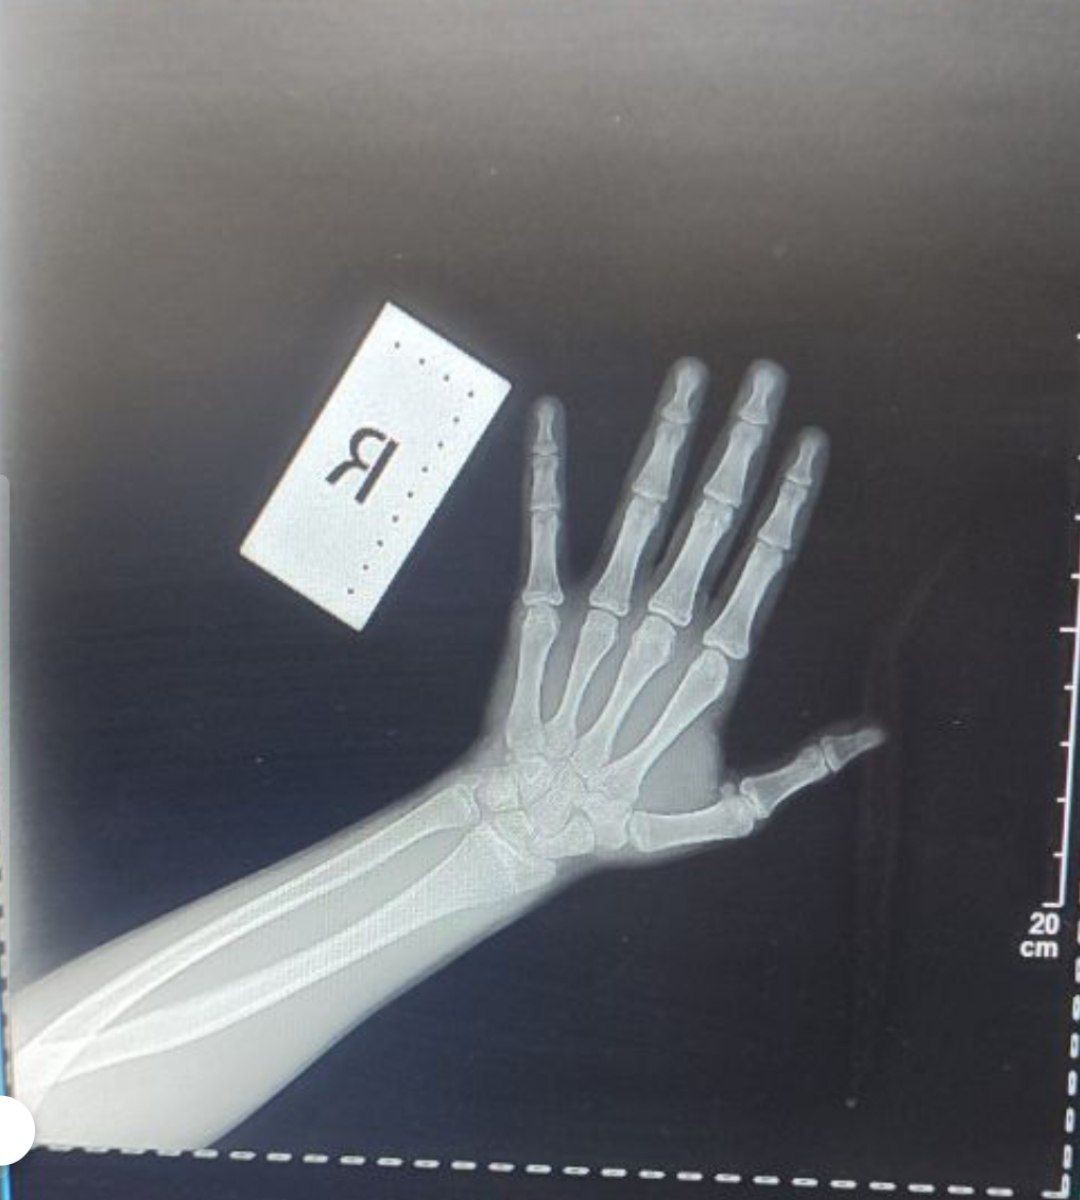

Зони росту

Спрашивает: егор

Пол: Мужской

Возраст: 16 лет

Вітаю, я робив знімок коли була підозра на перелом, це було у марте 2025 року мені тоді буле 15 років, я хочу дізнатись чи були у мене відкриті зони росту тоді і якщо вони були відкриті то чи можуть вони бути зараз відкритими? Мені вже 16 років і чи можуть вони бути ще відкри́ти на цей часе